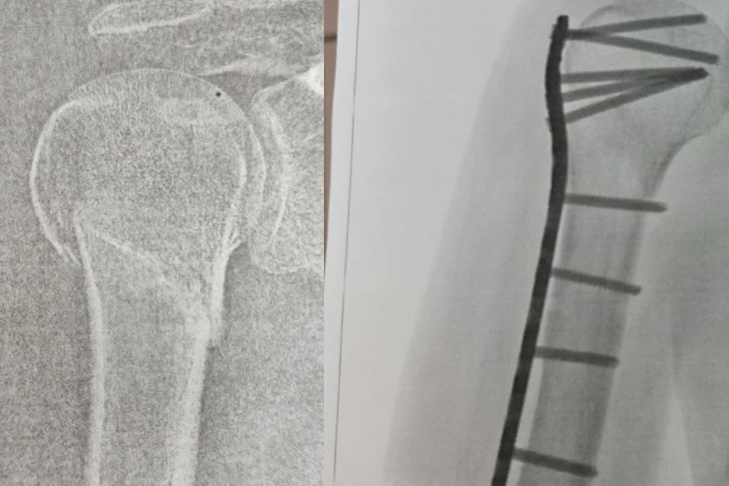

Муж Натальи вызвал скорую помощь. Медики забрали женщину, дали обезболивающее и наложили шину. В травмпункте рентген показал закрытый перелом плечевой кости со смещением отломков. Сибирячки пришлось проводить операцию — вставлять пластину и штифты.

«В марте выписали домой в гипсе. От слабости едва могла делать домашние дела, через 2 месяца гипс сняли. Правая рука висела «сама по себе», неподвижная, как будто после инсульта. Через боль я ее разрабатывала несколько месяцев», — продолжает женщина.

Через несколько месяцев Наталье удалось снять гипс, но рука безумно болела — пластина царапала кость. Металл пришлось доставать в частной клинике. В настоящее время женщина до сих пор проходит реабилитацию, а также пытается добиться компенсацию вреда от магазина.